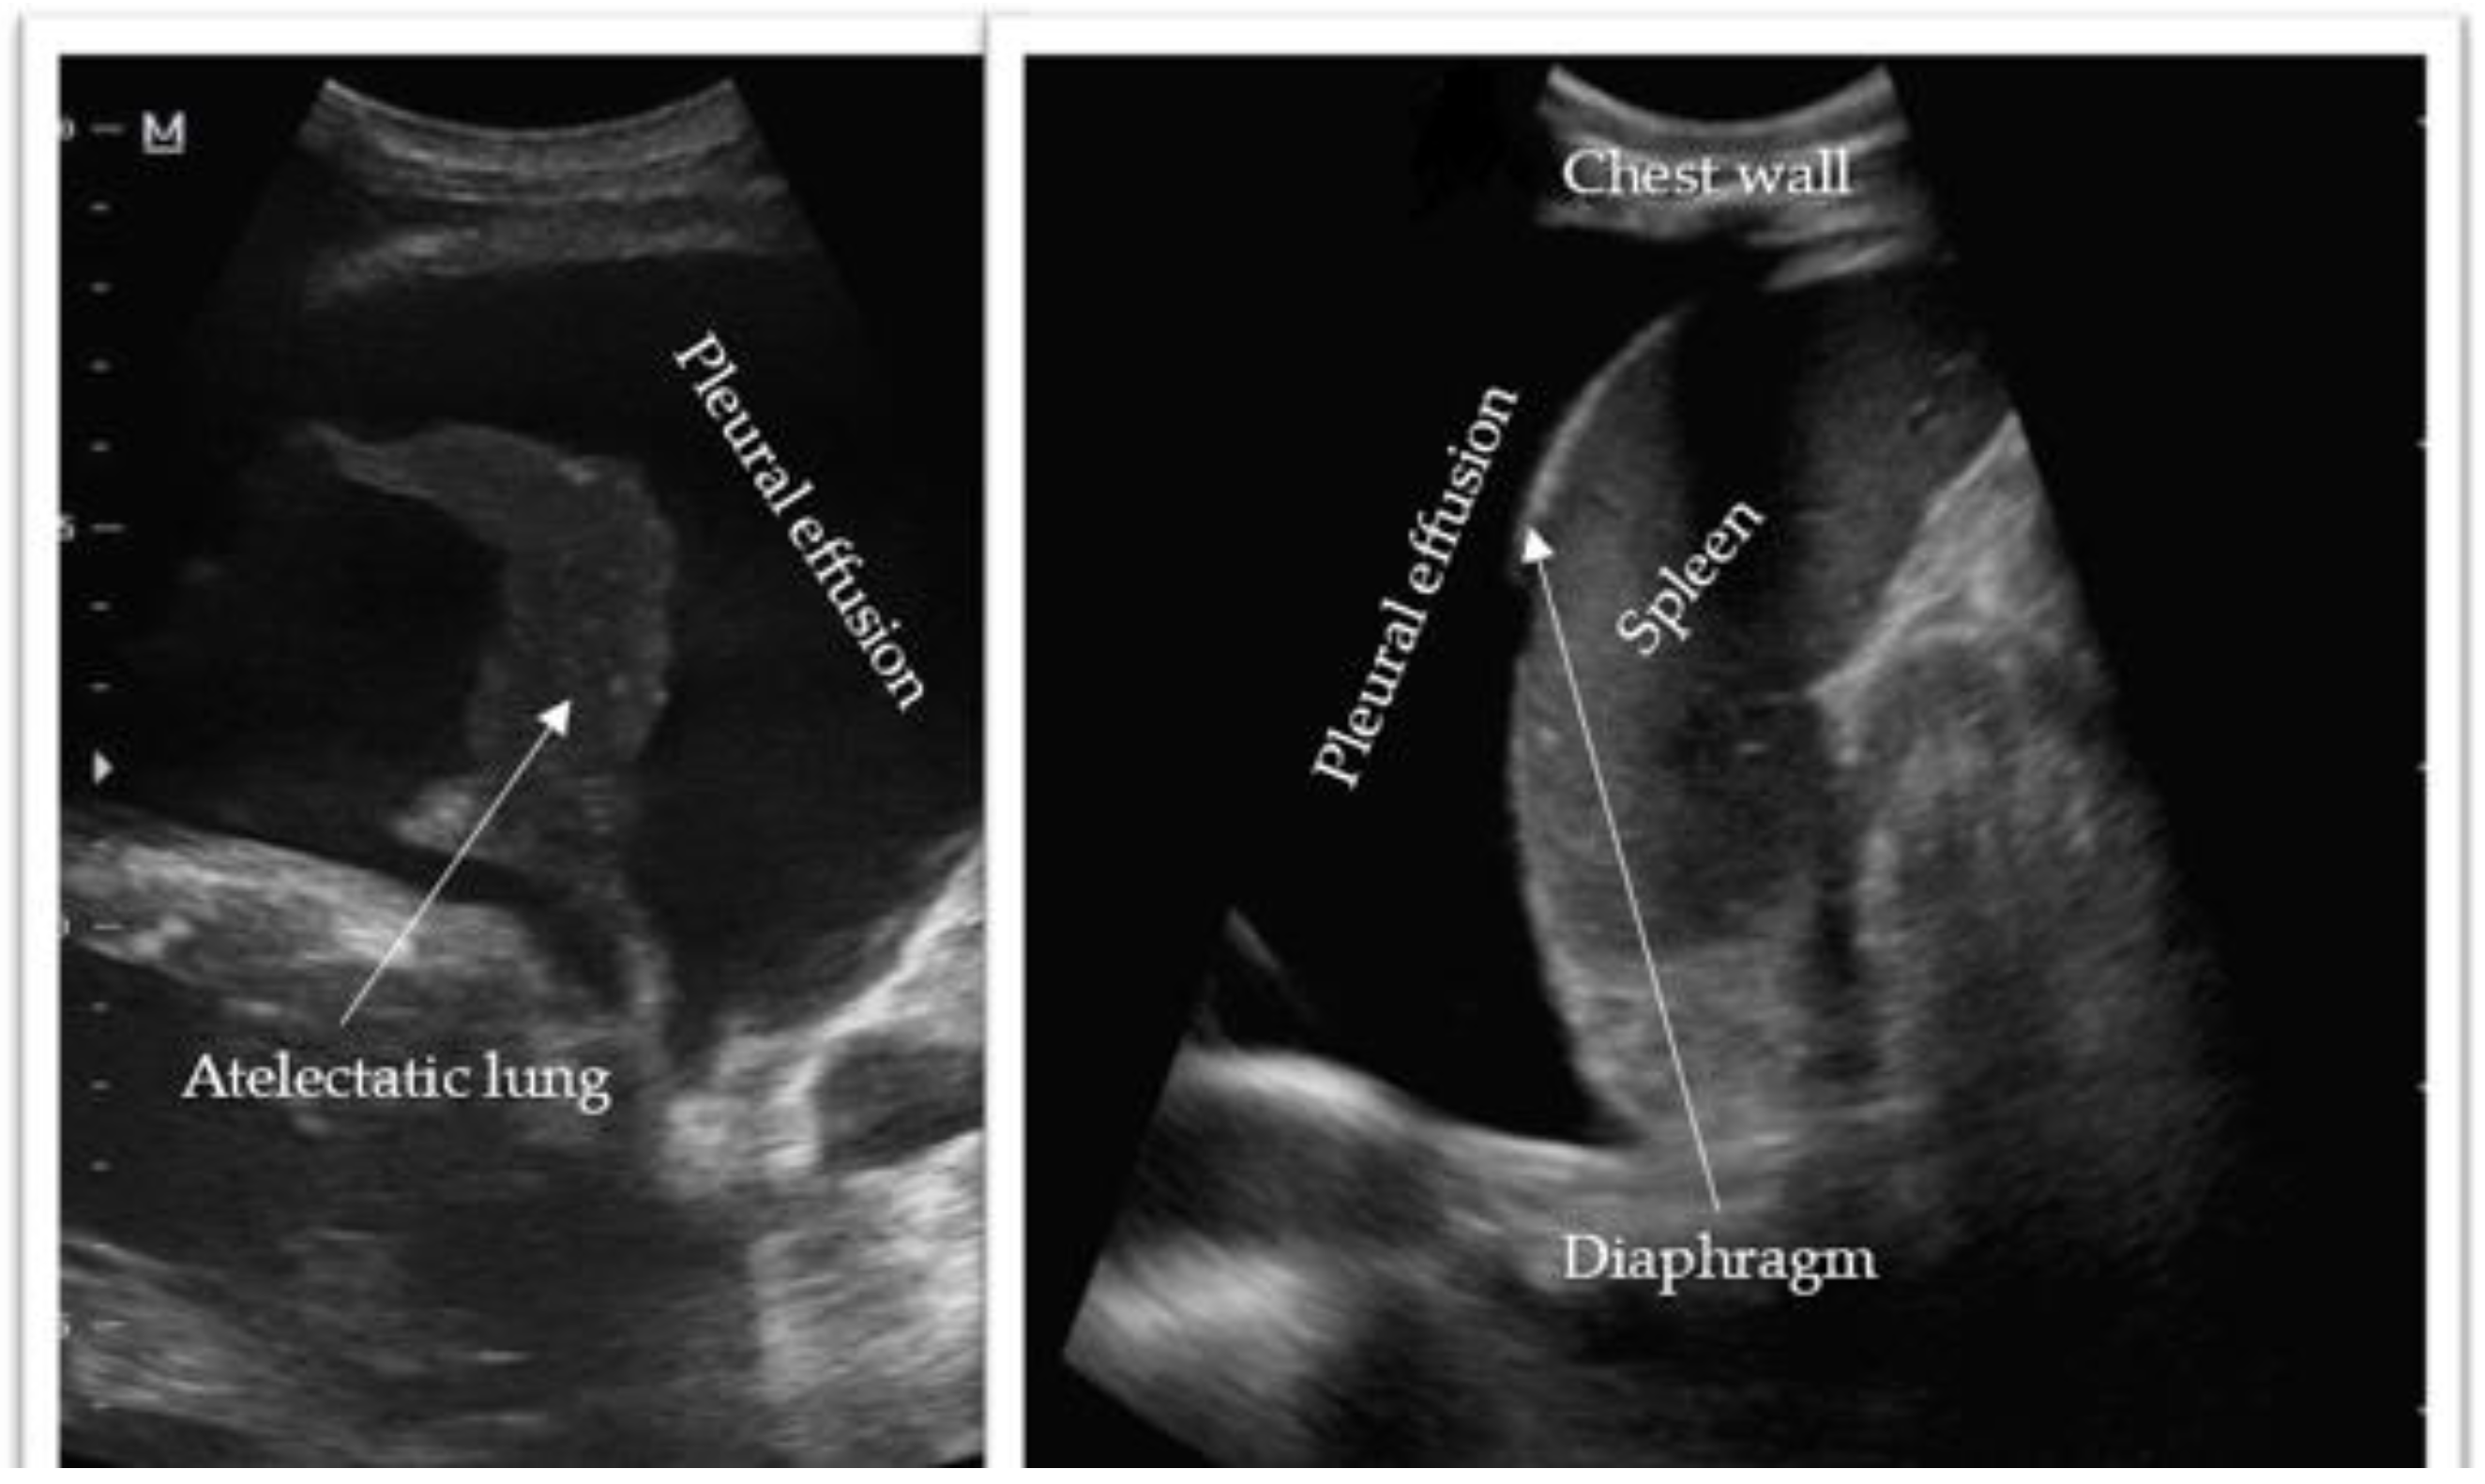

Thoracic ultrasonography has emerged as an invaluable diagnostic tool for assessing pleural effusions. Offering portability, noninvasiveness, and radiation-free imaging, it facilitates convenient and safe bedside evaluation (Figure 3). The accuracy of thoracic ultrasonography in detecting pleural effusions has been confirmed through numerous studies [8,9,10]. Notably, a 2011 study by Xirouchaki et al. reported 100% sensitivity, specificity, and diagnostic accuracy for thoracic ultrasound in pleural effusion diagnosis [9]. The International Consensus Conference on Lung Ultrasound supports this, asserting that “for effusion detection, lung ultrasound is more accurate than supine radiography and equally accurate to CT” [7,11]. Thoracic ultrasonography facilitates the assessment of fluid homogeneity, septation, and echogenicity. Several studies highlight ultrasound’s superiority over CT imaging in detecting intrinsic pleural effusion characteristics. Depending on the effusion’s etiology and complexity, four main sonographic patterns can be identified: anechoic (purely black), complex non-septated (black with white strands), complex septated (black with white septa), and homogenously echogenic (purely white) (Table 1) [7,12]. Complex appearances are typically associated with exudative effusions, while anechoic effusions can be either transudative or exudative. Echogenic effusions require drainage to explore for underlying etiology, such as empyema or hemothorax. Patient positioning significantly influences thoracic ultrasound evaluation [12]. Pleural fluid accumulates dependently within the thorax, making the seated upright position ideal as it encourages fluid movement to the lower thorax. In cases where patients face challenges or contraindications to upright positioning, such as mechanically ventilated critically ill patients, the supine position with the ipsilateral arm adducted across the chest toward the contralateral side is preferred [13]. Accurately identifying the diaphragm’s position relative to the pleural effusion is crucial to avoid diaphragmatic injury during drainage. Further discussion on the procedural role of thoracic ultrasonography will be provided in the subsequent sections.

Figure 3.

Thoracic ultrasonography demonstrating an anechoic pleural effusion with surrounding structures. Image (left) courtesy of Mohammad Osama Hussein Yonso, Radiopaedia.org, rID: 22793. Image (right) courtesy of Zhan Lim, Radiopaedia.org, rID: 94919.